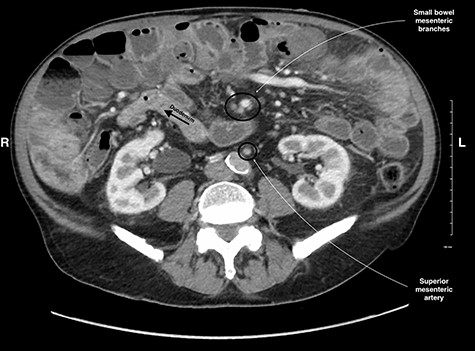

Midgut volvulus is an uncommon disease most often presenting in children, with rare occurrences in adults [3]. It is characterized by an abnormal rotation of the intestine around a fixed-point. Associated congenital conditions include gastrointestinal malrotation, jejunoileal diverticulosis and a history of abdominal wall defects [5, 6]. Acutely, volvulus can be intermittent or complete, with variable symptoms, leading to obstruction, bowel necrosis and possibly death. Chronic presentations of midgut volvulus can also occur, resulting in recurrent pain, intermittent obstruction and malabsorption over months to years. Due to its rarity in adults and variable presentation, preoperative diagnosis of intestinal volvulus is challenging. Adding to this difficulty, a classic ‘whirlpool sign’ or abnormal superior mesenteric vessel configuration is only present on CT in 30.9 and 58% of cases, respectively [3]. Retrospectively, the right-sided position of the duodenojejunal flexure and slight swirling of small bowel mesentery is visible but clouded by numerous jejunoileal diverticula (Figs 5 and 6).

CT image showing a subtle swirl of the mesenteric vein, coursing from the left to the right side of the abdomen indicating volvulus of the small bowel.